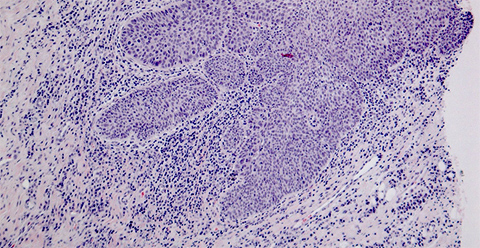

Histological picture showing a squamous cell carcinoma in a biopsy sample taken from a tongue.